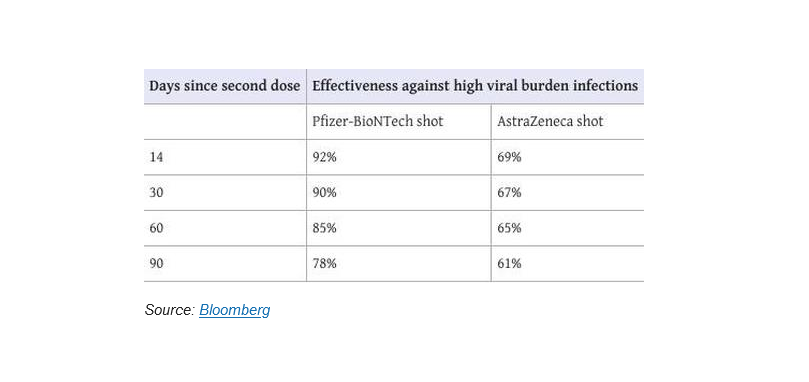

Π.χ. η αποτελεσματικότητα των εμβολίων της Pfizer ήταν 92% μετά από 14 ημέρες από τον εμβολιασμό, αλλά στις 90 ημέρες στους 3 μήνες είχε υποχωρήσει η αποτελεσματικότητα στο 78%.

Της AstraZeneca στις 14 ημέρες η αποτελεσματικότητα ήταν 69% και στις 90 ημέρες ήταν 61%.